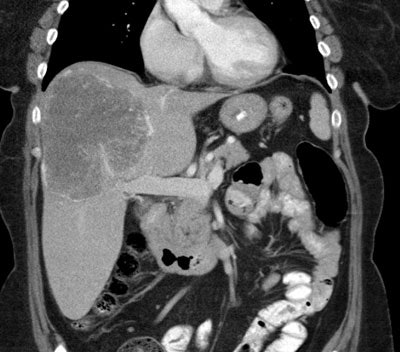

Liver malignancy:

Transarterial radiation therapy

with 90Y-microspheres is another potential treatment

method for hepatoma patients with low hepatic reserve [1] and in

patients with metastatic disease to the liver [5]. The dual

blood supply to the liver provides a natural selectivity for

tumor therapy [3]. Tumors generally derive their blood supply

from the hepatic artery, while the normal liver parenchyma is

perfused via the portal venous system [3]. When injected via a

branch of the hepatic arterial system, the microspheres

preferentially lodge in the periphery around the tumor [3]. The

preferential deposition of the microspheres in the tumor,

maximizes tumor irradiation while sparing adjacent liver

parenchyma [5]. After implantation, the 90Y-microspheres

remain permanently in place [3].

For patients with

hepatocellular carcinoma, current data suggest that

radioembolization is best placed after the failure of TACE in

the early intermediate-stage HCC or in patients with diffuse

disease (> 4 tumors) or large tumors (>5cm) [26].